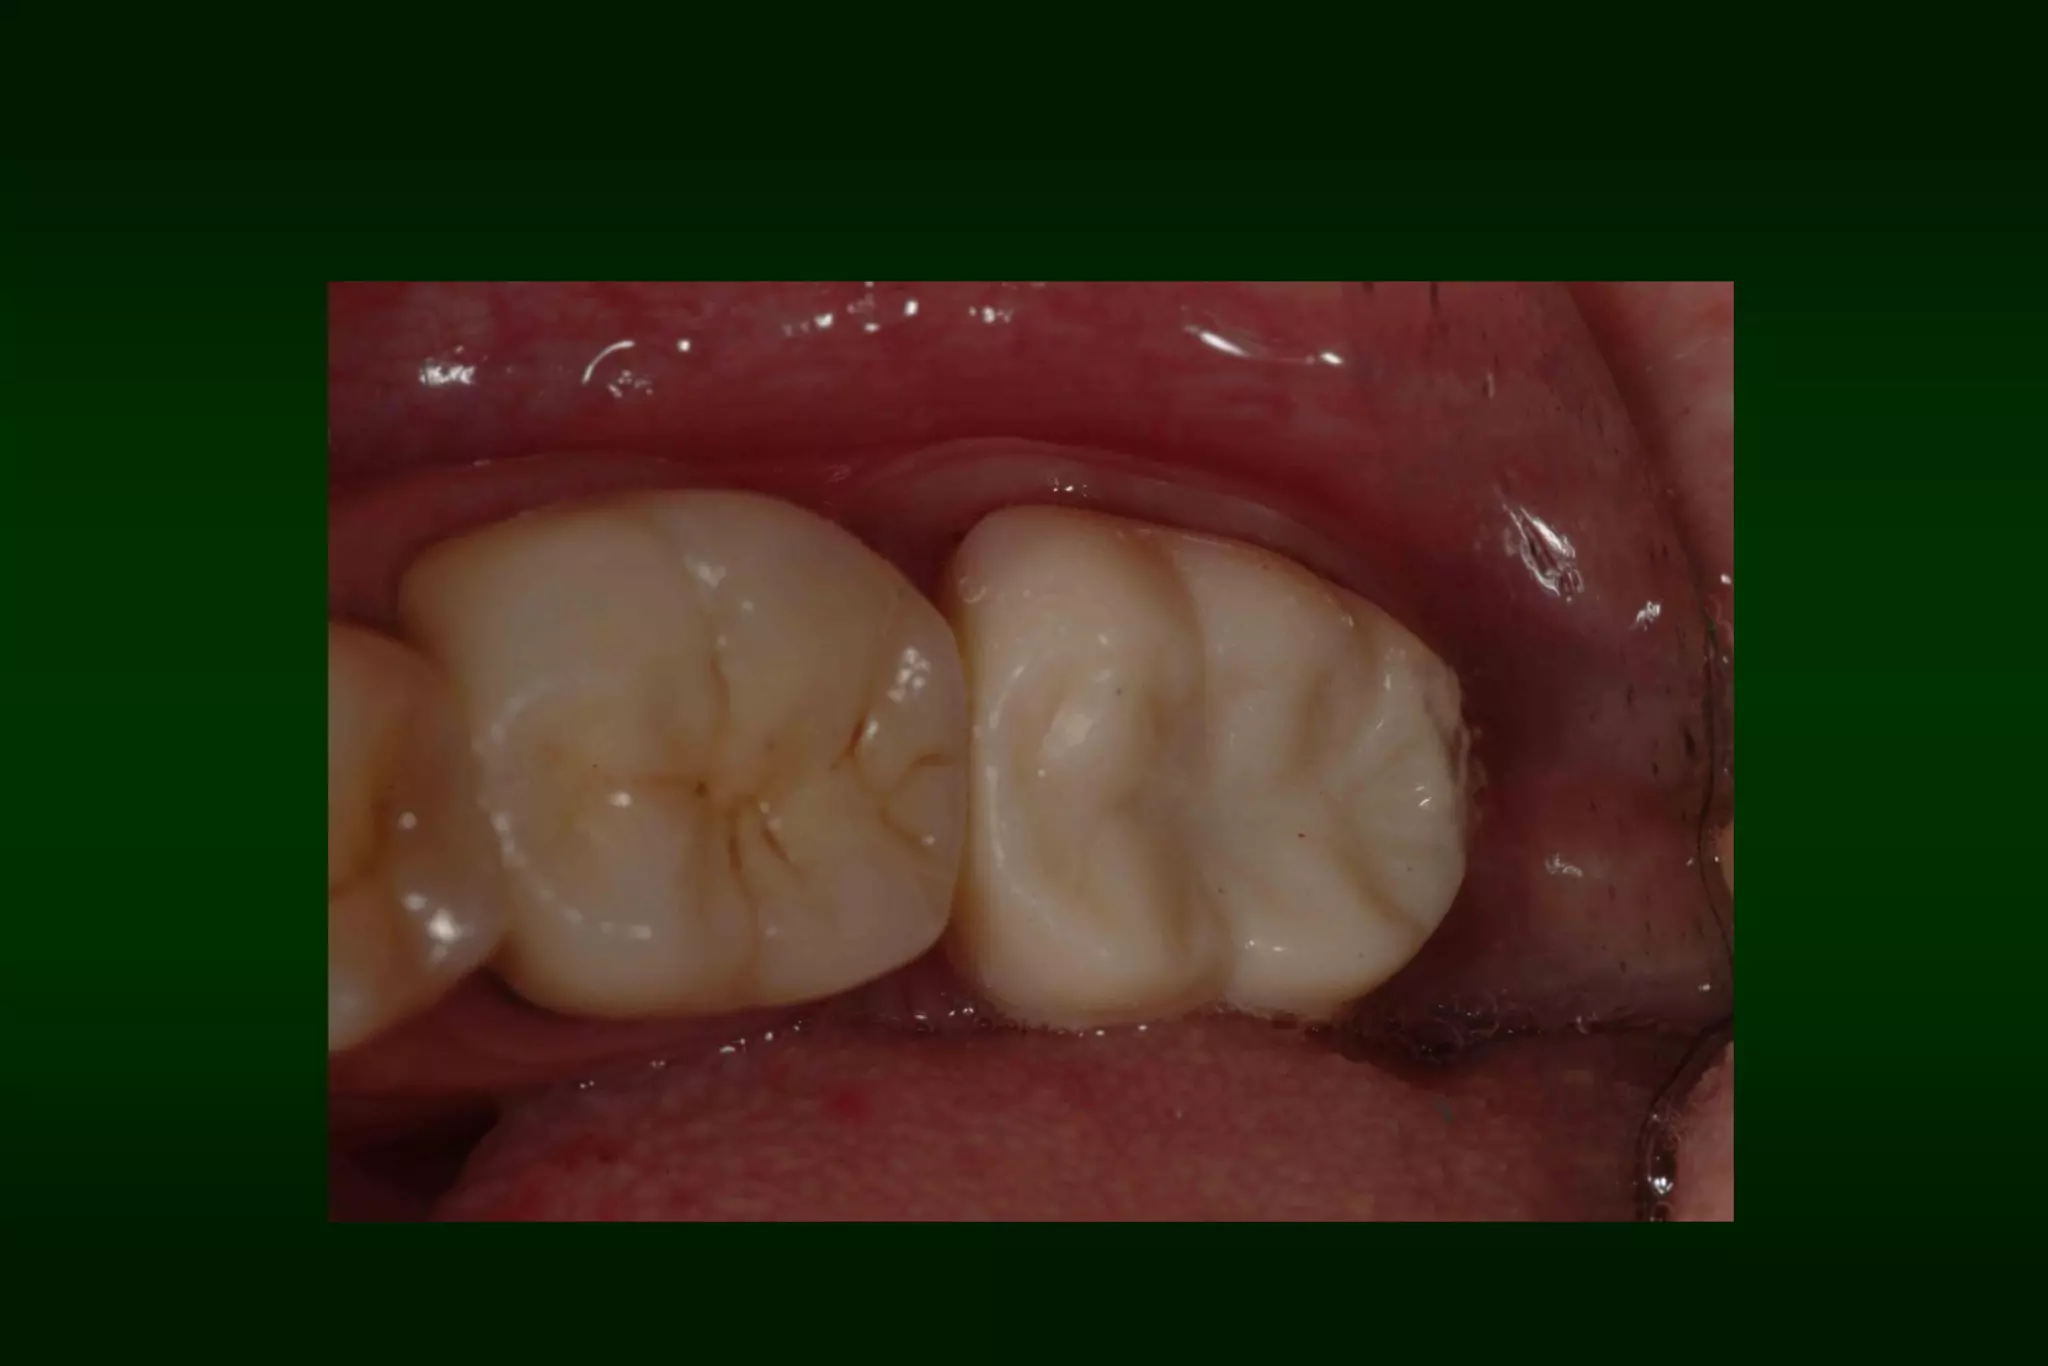

Requirements of Provisional Restoration I. Biologicrequirement: • • • • • Protect the dental pulp Maintain and contribute to the periodontal health Provide comfortable, functional occlusal relationship Maintain tooth position Protect remaining tooth structure

After 1 week

After 2 months